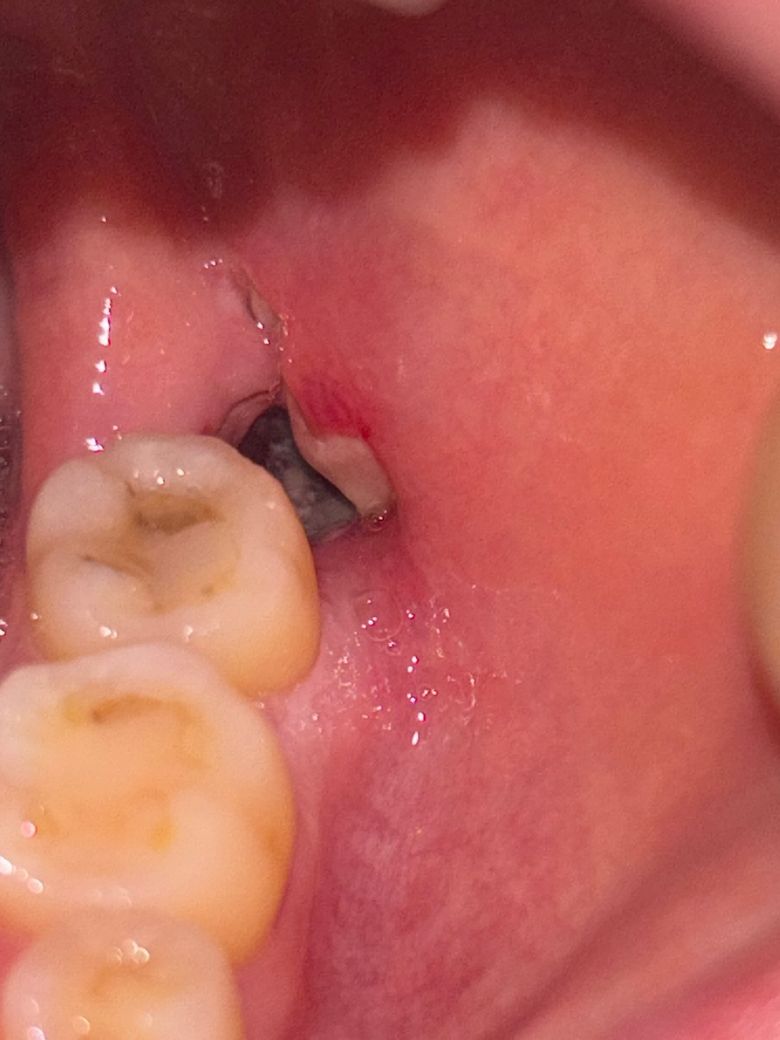

사랑니 발치 후 구멍속 흰색 음식물인가요..

잇몸위로 전혀안올라온 매복 사랑니 발치했고

꼬매지는 않았습니다..

구멍속과 입구에 흰색이 보이는데..

입구쪽은 헐은건가요?

안에는 음식물일까요?..

지금까지 밥이랑 치킨이랑 반대편 이로 다 씹어 먹었어서.. 음식물이 끼였으면 어떻게 해야할까요

지금 큰 통증은 없는데 밥먹고나서부터 좀 이물감이랑 통증이 생기고있는것 같기도 해요..

• 1번 째 사진

사랑니를 발치하고 나면 발치한 부위에 빈공간이 생기기 때문에 이물질이 낄수 있습니다.

이런 이물질은 가볍게 가글을 해서 제거를 해주는것이 좋으며 시간이 지나면서 잇몸이 아물게 되면 끼는것이 줄어들게 됩니다

잘 빠지지 않는 다고 무리해서 제거를 하거나 수압을 가해서 제거하지 않는것이 좋으며 치과에서제거를 해야할수 있습니다.

매복 사랑니 발치하느라 고생하셨습니다 사진상으로 해당 부위 정확히 보이지는 않으나 사랑니 발치 후에 발치 된 공간(구멍)에 혈액이 차고 혈액이 굳어가면서 혈병 이라는 것을 만드는 과정으로 보입니다 지금처럼 반대편으로 음식 드리고 관리 잘 해주시면 전혀 문제 없습니다 정상 치유 과정이니 걱정마세요

1. 입구는 염증같고, 내부 물질은 염증,육아조직 같습니다.

2. 처방받은 진통제 드시기 바랍니다.